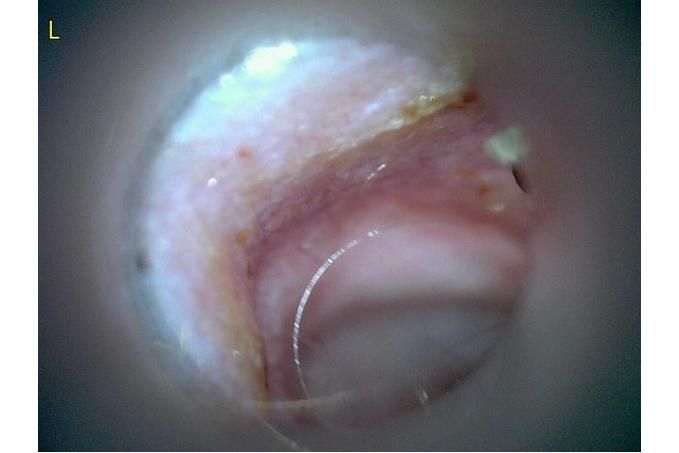

오늘 낮과 방금 5분전에 일어난 일인데요.. 강아지 귀질환 중에.. 옷입히고나서 귀를 바닥에 대고 비비거나, 귀에 통증을 호소하면서 잠깐 비틀비틀 걷는 경우 이런 경우 대체 뭘까요? 외이염일때도 이럴수도 있을까요? 아니면 중이염 내이염일지.. 한 2~3분정도 통증을 호소하다 지금은 또 정상이 됬는데 옷입을때만 옷의 목카라 부분이 귀에 닿을때 문제가 되는 느낌입니다. 평상시엔 가끔 양쪽 귀를 긁거나 귀를 자주 터는 정도입니다. 특이사항은 오른쪽귀 솜 돌돌 말아 귀안에 넣어줘도 비명을 지르며 엄청 아파하는데(작년11월경) 왼쪽은 안아파합니다)

그리고 용종이라고 코멘트 달아주셔서 저 검이경 사진 찍은곳에 물어보니 용종은 아니라고합니다.

저 부분 용종 아니라합니다

제가 가장 알고싶은점은. 저렇게 옷깃에 귀가 시쳐도 아파할정도면 이게 외이염일까요 중이염일까요 내이염일까요? 얼마나 아픈지 옷한번 얇은 내복 평상시 입던거 입히면 입히고 나서 바로 온집을 돌아다니면서 바닥에 귀를 대고 정신나간애처럼 비비고 비틀비틀 걷습니다 그러다가 2~3분후 다시 정상으로 돌아옵니다

(근데 또 귀를 조물락 조물락 만져도 안아파합니다, 다만 솜을 길게 해서 넣으면 솜만 넣어도 아파합니다 특히 오른쪽요 왼쪽은 안아파합니다)